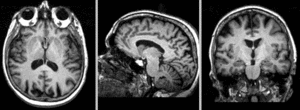

v3.6.1 Slicer3-6Announcement-v1.png Slicer Registration Library Case 18:

Serial Multi-contrast MRI in Aging Study

lleft lleft lleft lleft

exam 1: T1 exam 1: FLAIR exam 1: T2